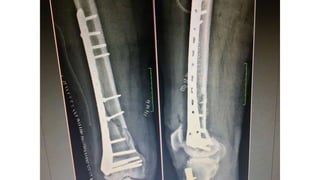

Locked Plate Fixation

• Indications:

Fixed-angle locked screws provide improved fixation in short distal

femoral block

• technique:

Lag screws with locked screws (hybrid construct)

Useful for intercondylar fractures (usually in conjunction with locked plate)

Useful for coronal plane fractures .

Helps obtain anatomic reduction of joint

Required in displaced articular fractures